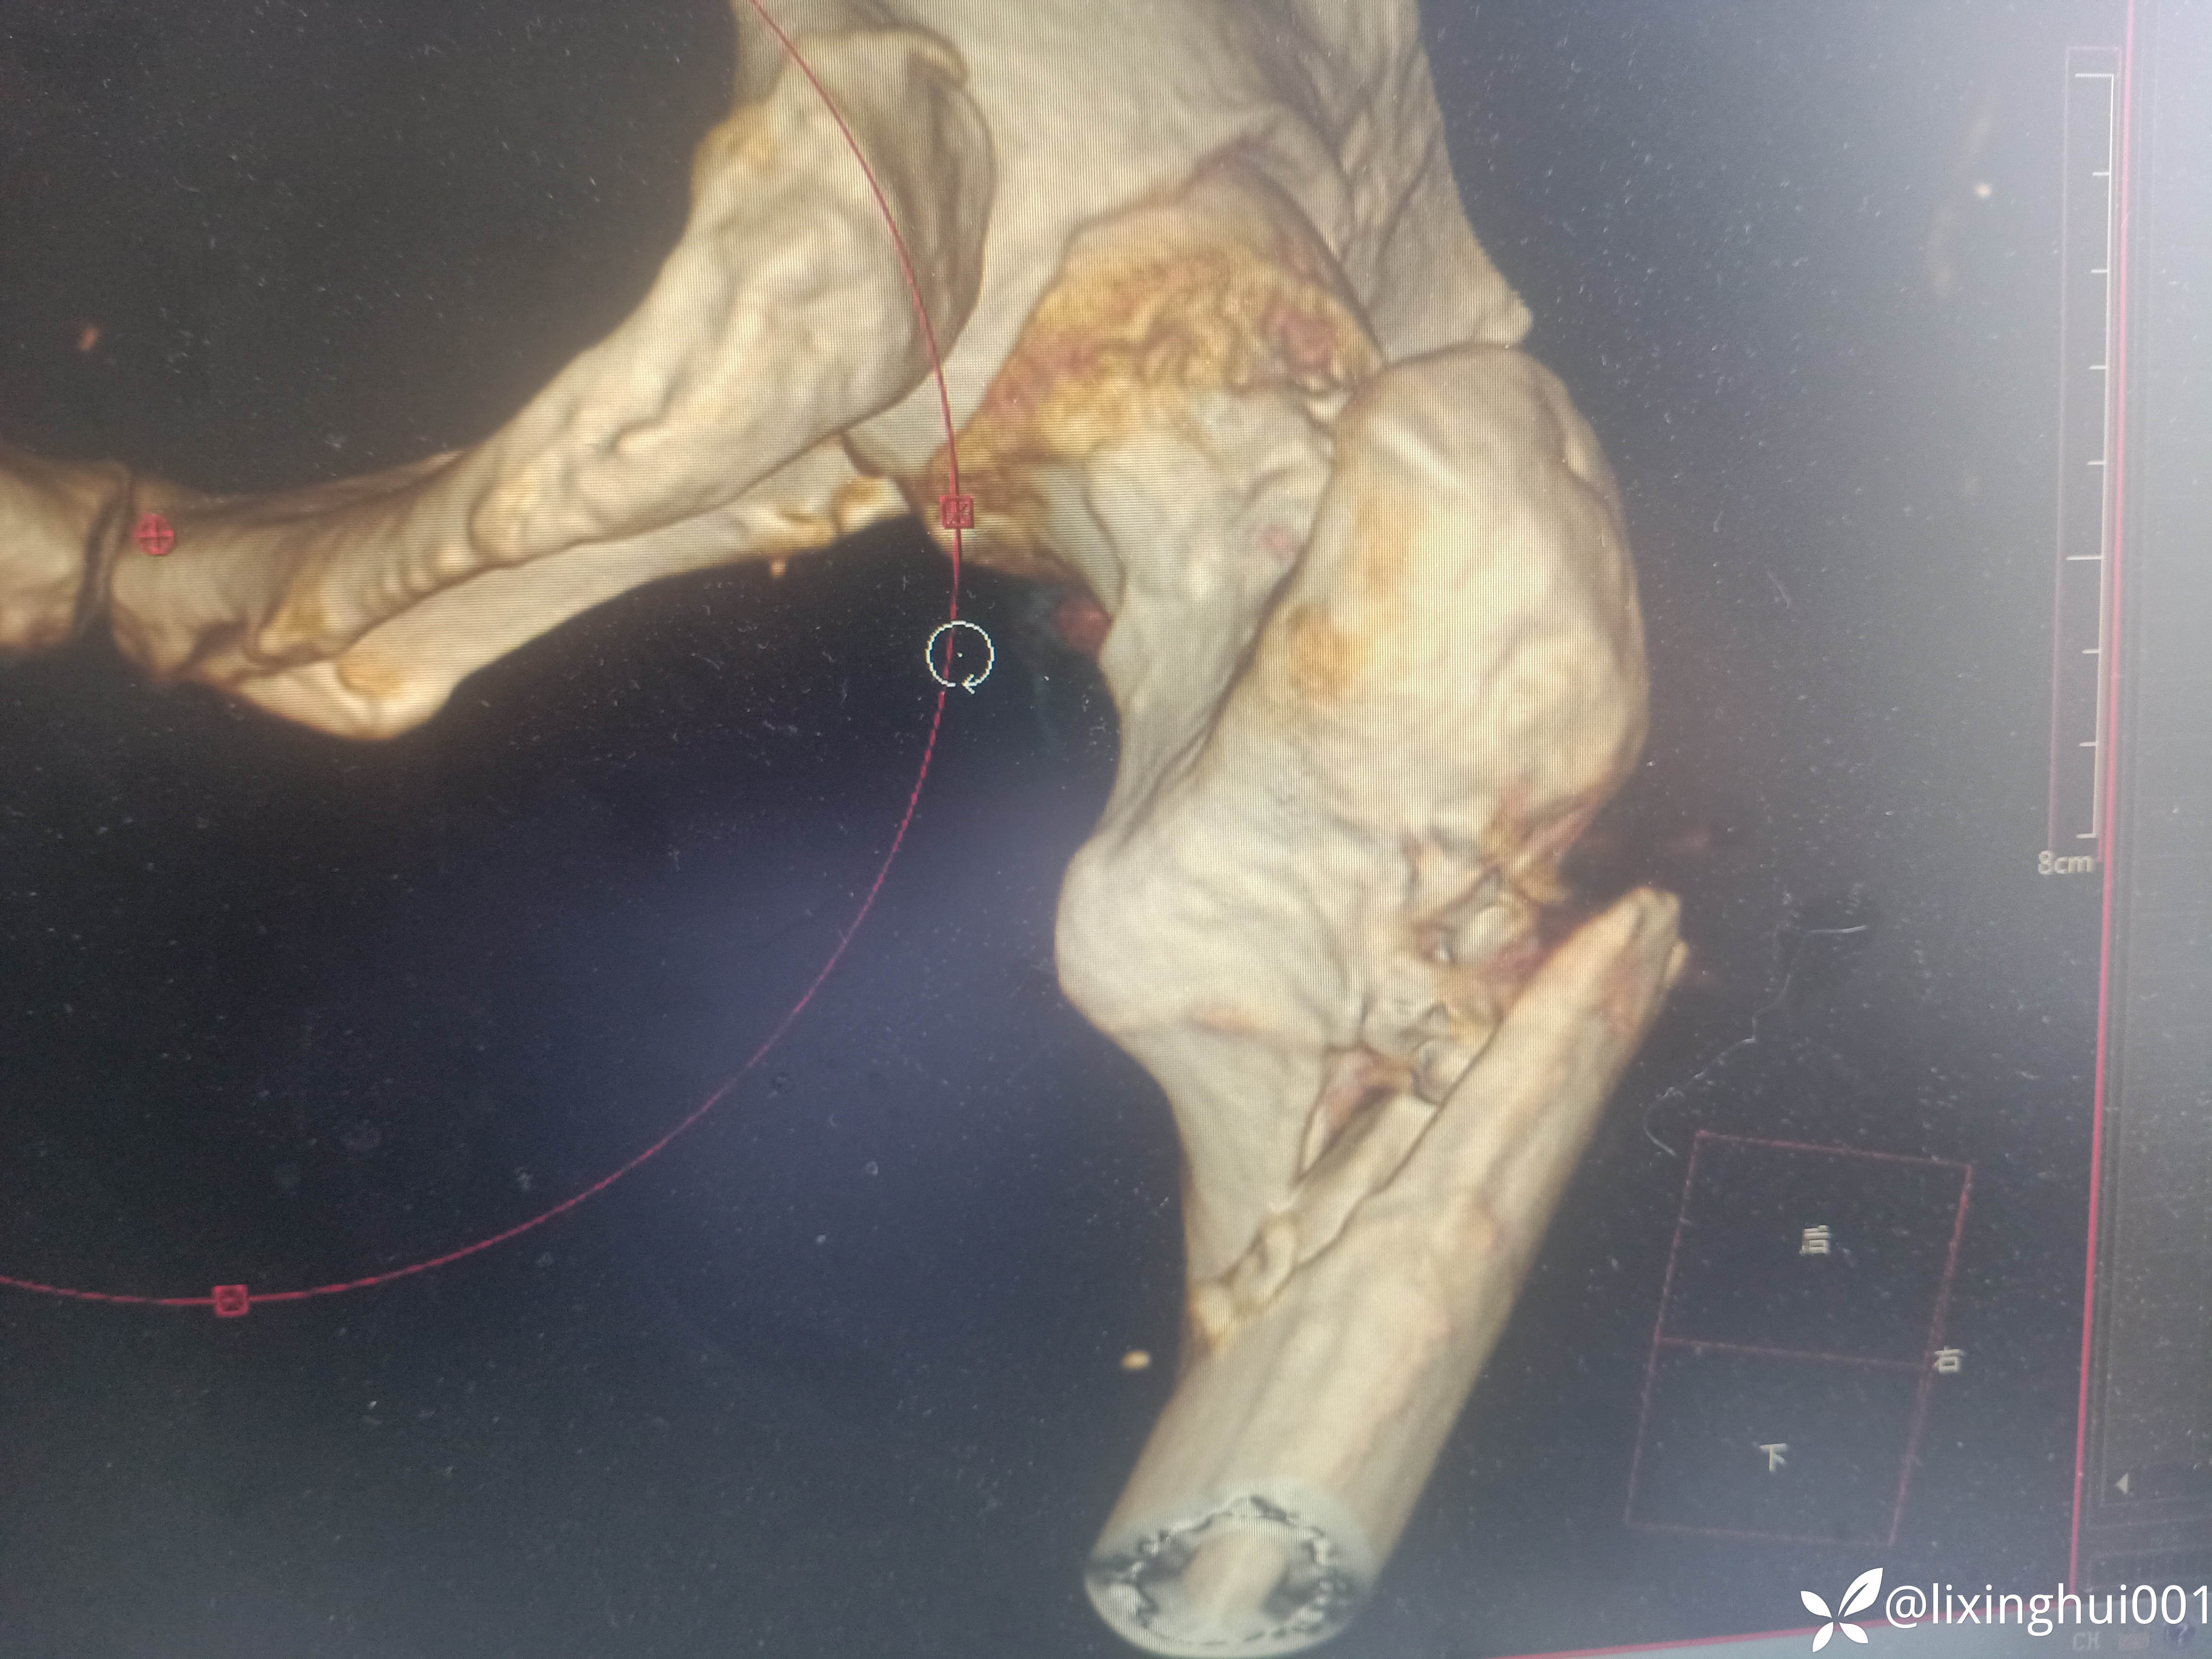

56岁股骨颈骨折术后股骨近端再次骨折

【患者信息】:56岁男性,40天前因右股骨颈骨折于外院行闭合复位螺钉内固定术,不慎再次摔伤来诊

【临床诊断】:右股骨颈骨折术后,→股骨近端骨折

考虑患者年轻,没有股骨头坏死,暂时予以内固定治疗,术后发生股骨头坏死,再行置换。要是年龄较大,同时股骨头有坏死发生,一期加长柄置换是否可行。